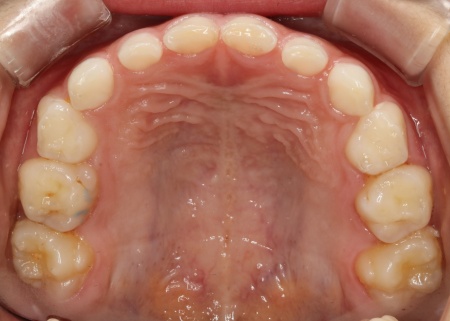

まずは上顎に「バイオブロック(BB1)」という装置を装着します。

バイオブロックとは、上顎の骨を前方に成長させることを目的とした、乳歯列期のお子様に適した矯正装置です。この装置により、上顎の骨の成長を促して反対咬合の改善を図りました。

続いて下顎には、顎の幅を広げて歯が並ぶスペースを確保しながら、上下の噛み合わせのバランスを整える役割をもつ「拡大床」という装置を装着しました。

治療中